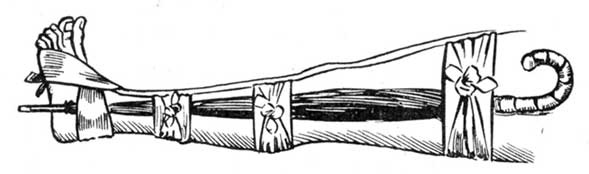

When the bath has done its work, and the limb comes out of the water alarmingly swollen, good and skilful bandaging will do excellent work. If you have at hand an old shirt, or some such thing, tear it into strips about three inches wide, till you have as much material as will swathe the whole limb from behind the toes up to the top of the thigh. This need not be all in one piece, but only so that you may apply it in such a way as to bring a very gentle pressure on the whole surface of the injured limb. It is important that the bandaging should be comfortable. The way in which bandaging is sometimes done is cruel in the extreme. Cases that are a disgrace to humanity are constantly coming under our notice, in which limbs are lost for life by the treatment they receive in this respect. Skilful surgeons do it in the most gentle manner; they even swathe the limbs in soft loose cotton before they apply the bandages, so that a perfectly equal and comforting pressure may be secured. Lay the limb to rest, well and softly supported in a horizontal position. When the swelling falls, gently tighten the bandage from time to time as required. Each time the bandages are removed for this purpose, sponge the limb with warm vinegar or weak acetic acid (see). When the swelling subsides, the ankle may be put again in the hot bath for half-an-hour, and then, if any bones be broken, is the time for setting them right. The ankle will probably turn black. If so, do not apply leeches, but allow the black blood to be absorbed by natural process.